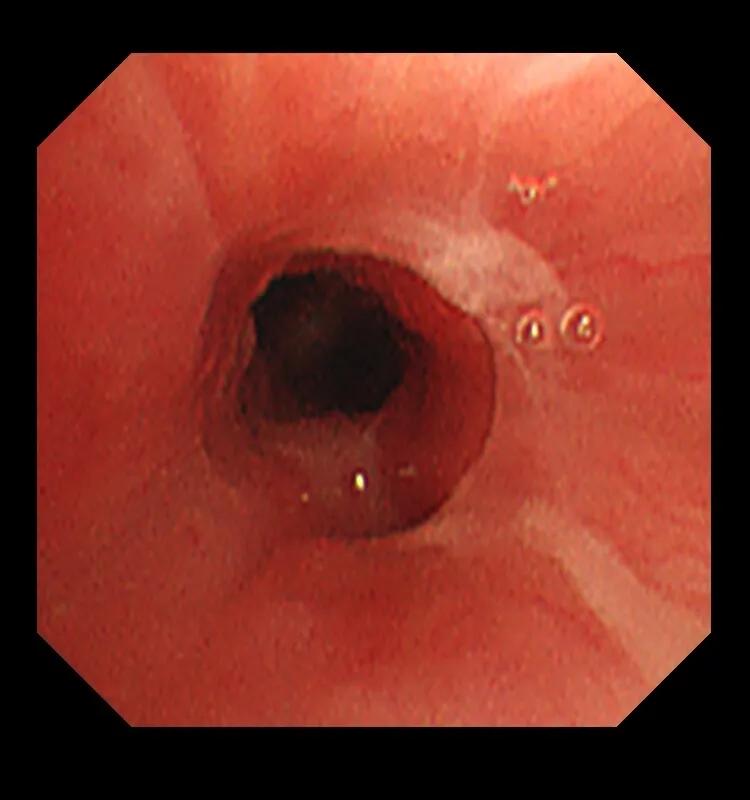

为了进一步明确是不是真的存在异物,预约了全麻完善了电子支气管镜检查,结果......

电子支气管镜检查提示左下叶腔内真的被一东西堵住了,究竟是什么?!

取出异物后,管腔就通畅,远端分泌物就引流通畅了,这个异物其实是花生小碎块。